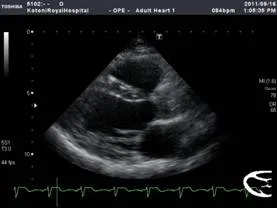

心エコー(心臓超音波)

身体の表面に探触子という部品を当てて、心臓の形や働きを観察する検査です。痛みは無く、検査時間も15~20分程度で終わるので、患者さんの負担が少ない検査 です。心臓肥大は無いか、心臓が弱っていないか、などが分かります。

心エコー図:Bモード(左)、カラードプラ(右)